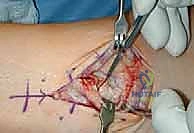

2. الوصول الجراحي الدقيق

يقوم الدكتور هطيف بعمل شق جراحي دقيق في الجزء الأمامي من الكاحل. بفضل خبرته في الجراحة الميكروسكوبية، يتم إبعاد الأوتار والأعصاب والأوعية الدموية بحذر شديد لحمايتها من أي ضرر.

3. تحضير العظام باستخدام أدوات التوجيه

هنا تبرز روعة نظام INBONE™. يتم استخدام أدوات توجيه خاصة (Jigs) لضمان المحاذاة المثالية. يقوم الجراح بإزالة الأجزاء التالفة من غضروف وعظم الظنبوب (Tibia) والقعب (Talus) بدقة متناهية بالملليمتر.